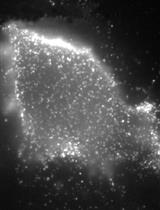

This protocol has merit to observe the subretinal microglia or macrophages (Figure 5), which are separated to retina and/or choroid/RPE whole mounts in the general protocol. See additional resources for a demonstration of subretinal microglia and extended processes (Kim et al., 2016).

Figure 5. Subretinal microglia in Sclerochoroid/RPE/Retina whole mount. Sclerochoroid/RPE/Retina tissues are labeled by phallodin-488 (green), CD11b antibody (red) and Hoechst 33342 (blue). Images were captured from choroid/RPE to the upper level of photoreceptor layer, every 2 μm z-interval. A. A projected image. B. Images arranged at 4 μm interval. Arrow heads indicate migrating/extending processes of microglia from the photoreceptor layer to the subretina. Ph, photoreceptors; RPE, retinal pigment epithelium. Scale bar, 50 μm.